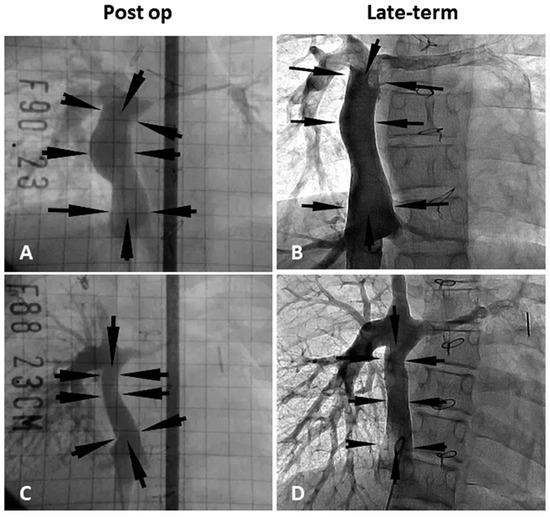

- Hibino, N.; McGillicuddy, E.; Matsumura, G.; Ichihara, Y.; Naito, Y.; Breuer, C.K.; Shinoka, T. Late-term results of tissue- engineered vascular grafts in humans. J. Thorac. Cardiovasc. Surg. 2010, 139, 431–436. [Google Scholar] [CrossRef] [PubMed]

- Sugiura, T.; Matsumura, G.; Miyamoto, S.; Miyachi, H.; Breuer, C.K.; Shinoka, T. Tissue-engineered Vascular Grafts in Children With Congenital Heart Disease: Intermediate Term Follow-up. Semin. Thoracic. Surg. 2018, 30, 175–179. [Google Scholar] [CrossRef] [PubMed]